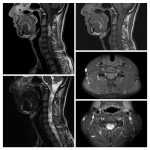

Neurosurgery and neuroradiology always go hand in hand. This little weekly activity is going to enhance the scan reading skills of our audience in an interactive way. Waiting for the answer for a week will keep the curiosity alive and will keep our target audience hooked to the website. It will prove to be a seamless share of knowledge and reading skills.

Dr. Saqib Kamran Bakhshi started the PANS Weekly Image Challenge in 2022, and his creativity and efforts made it a popular activity; engaging trainees and consultants in Pakistan and abroad.